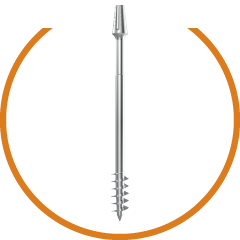

Allow insertion in minimum 1-2 drilling. Optimum Zygomatic bone engagement. Micro-polished tip without any sharp edges.

Measurement Information